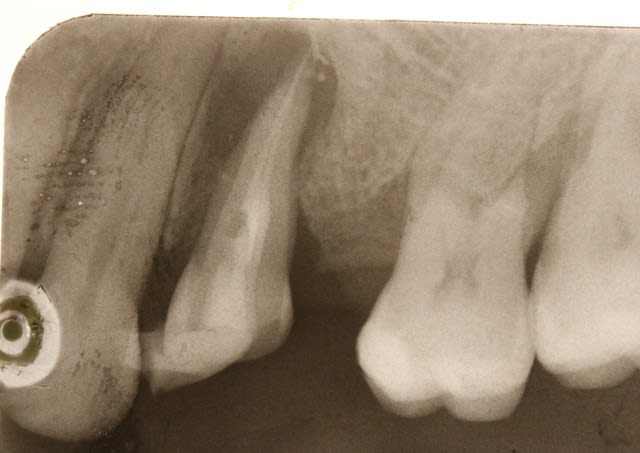

voilà des nouvelles du dernier cas .

je me suis trompé ,je ne l'ai pas enlevé debut janvier mais le 12 fevrier . on est donc à 1 mois

aujoud'hui , il n'y a pas de douleur ,la dent bouge un peu ( comme les autres dents ),il n'y a plus eu d' abces purulent .

la sonde paro rentre en distal .

la cale en occluson est tjs là , la dent n'etant pas collée à la canine .

la patiente est ravie , mais moi je le sens moyen ce coup !

ç est bien beau de la garder cette dent , mais pour en faire quoi ? ç est un plan à la con :-)

ce qui n'empeche qu'elle est tjs là , et on se demande bien pourquoi :-)).